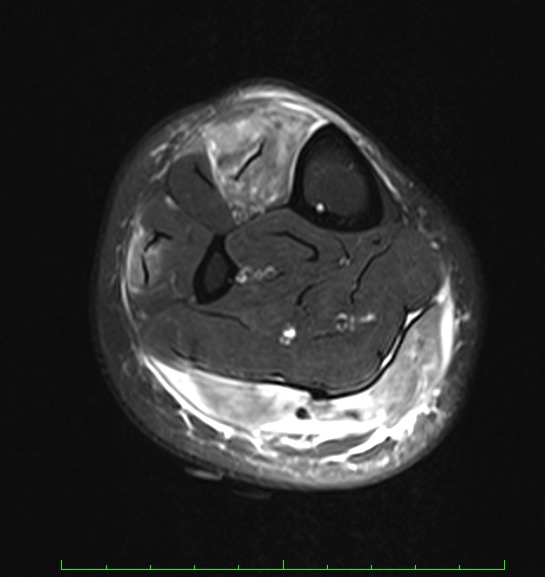

Findings of the initial workup by the primary care provider were negative for deep vein thrombosis on Doppler ultrasonography and negative for arterial insufficiency on ankle-brachial pressure index. Electromyography findings were negative for myopathic or neuropathic abnormalities. Magnetic resonance imaging (MRI) scans of the lower extremity showed hyperintensity on fat-suppressed T1-weighted images of the musculature with associated subcutaneous nodularity (Figures 1 and 2).

Figures 1 and 2. MRI scans of the right lower extremity showed nodularities and nonspecific inflammation within the leg muscles, particularly the tibialis anterior and gastrocnemius muscles.

As illustrated by this case, the diagnosis of muscle-limited vasculitis can be extremely challenging. MRI can aid in the diagnosis by showing increased signal intensity in the affected calf muscles and subcutaneous tissue on fat-suppressed images, which indicates edema from an inflammatory process.4-7 Moreover, MRI findings give clues as to which area of the muscle must be biopsied and also can guide response to therapy. All of the reviewed cases of muscle-limited vasculitis involve the lower extremities. Most often, the gastrocnemius and soleus muscles are involved.2,4-7 MRI comparison images in one case report have shown decreased signal intensity after treatment.4